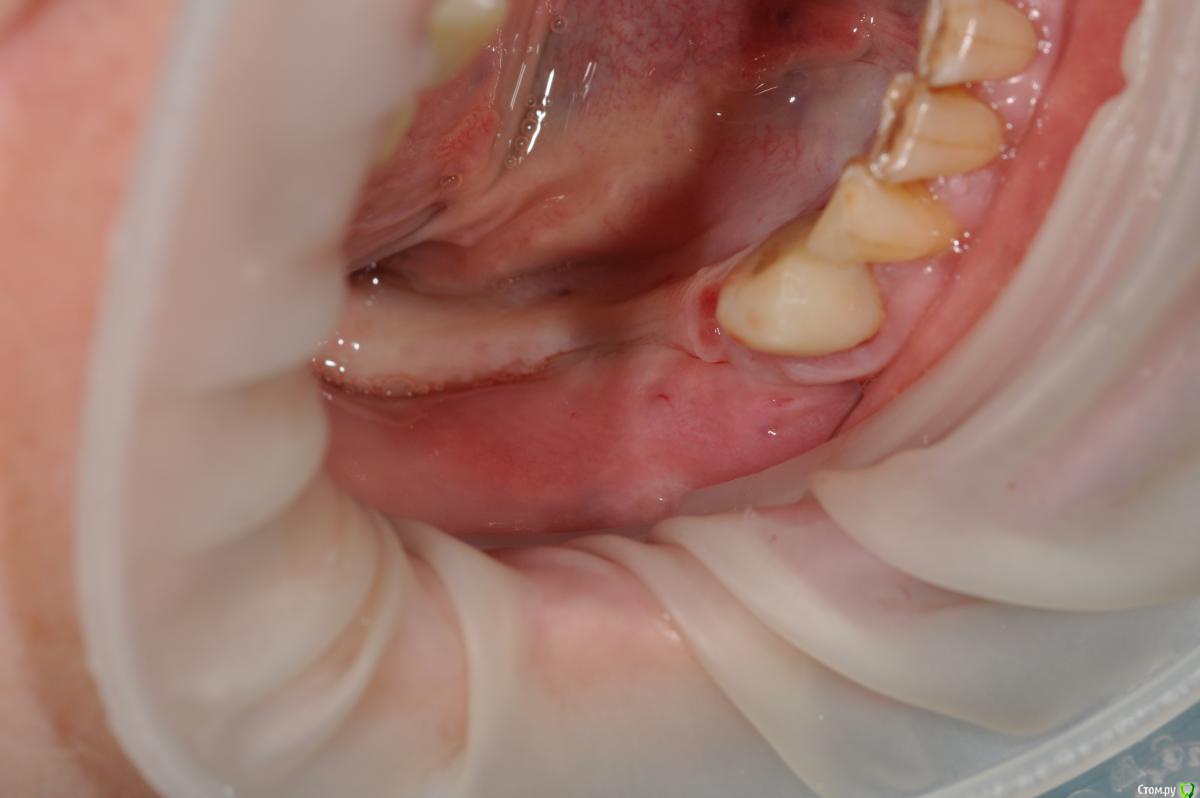

kamranchick Опубликовано 16 ноября, 2018 Поделиться Опубликовано 16 ноября, 2018 Господа, Как вы решаете вопрос с отсутствием зкпд в полном обьеме.у пациенки жалобы на то что" при поднятии языка, дна полости рта поднимается и нализиет на формирователь десны, соответственно на протезирование я пока не хочу передавать.в течении 3 недель у пациентки выросла шишка под языком в области 3 6 зуба...убрал формирователь и поставил заглушку.Видел у Ильгама как он делал зкпд, не скинете видео? не могу найтии что делать с этой шишкой и как вести пациента? спасибо 1 Ссылка на комментарий

kamranchick Опубликовано 17 ноября, 2018 Автор Поделиться Опубликовано 17 ноября, 2018 Протезирование помогает.Была пациентка .И чего я только ей не делал...После постановки короткого формирователя стало немного лучшеБыло решено запротезировать.Помогло у меня прям похожая картина, пациентка даже умудрилась ободрать язык об этот формирователь, из за этого пришлось заглушку ставить,плюс шишка какая то стала Ссылка на комментарий

Neilrus Опубликовано 17 ноября, 2018 Поделиться Опубликовано 17 ноября, 2018 ну у вас ситуация понятная.... не такая тяжелая, а тут вообще ее нет, даже если бы была язычно 1.5 мм. было бы намного проще. она бы на месте оставалась бы при движении языком туда сюда, в моем случае, любое движение языком это катастрофаА есть фото? прямо дно переходит в щеку? Есть гребень хотя бы?Если так, то я бы сначала создал толщину с помощью сст, потом прикрепленку полнослойным...еще тут мотивация важна пациента, конечно, у меня даже после фоток не всегда пациенты на 100% понимают смысл повторных операций, для них-то все едино Ссылка на комментарий

kamranchick Опубликовано 18 ноября, 2018 Автор Поделиться Опубликовано 18 ноября, 2018 А есть фото? прямо дно переходит в щеку? Есть гребень хотя бы?Если так, то я бы сначала создал толщину с помощью сст, потом прикрепленку полнослойным...еще тут мотивация важна пациента, конечно, у меня даже после фоток не всегда пациенты на 100% понимают смысл повторных операций, для них-то все единотолщину создать то не проблема, а прикреплению куда будете фиксировать? я рассматривали вариант прибить СДТшматок к кости, но после слов Большого Зеленого теперь думаю стоит ли туда лезть Ссылка на комментарий